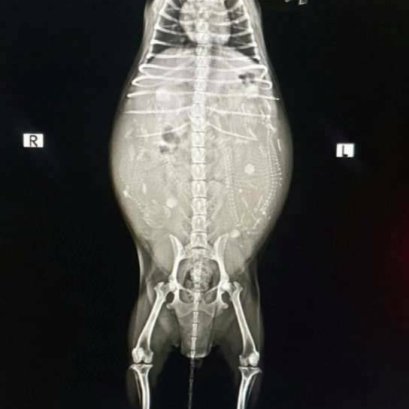

แมวผมนอนตะแคงแล้วจะเห็นก้อนปูดๆที่ท้องครับหมอ สงสัยว่าน้องจะเป็นฝี หมอคลำดูไม่มีก้อนฝีที่ผิวหนังนะคะ คลำเจอแต่ไต พบ 2 ข้างเลย มีขนาดใหญ่ เจ้าของยังสงสัยคุณหมอจึง x-ray ช่องท้องดู พบว่าไตมีขนาดใหญ่กว่าปกติ จึงต้องตรวจเลือดและ ultrasound ช่องท้องเพิ่มเติม ผลปรากฏว่า น้องเป็น ถุงน้ำในไต (Polycystic Kidney Disease)